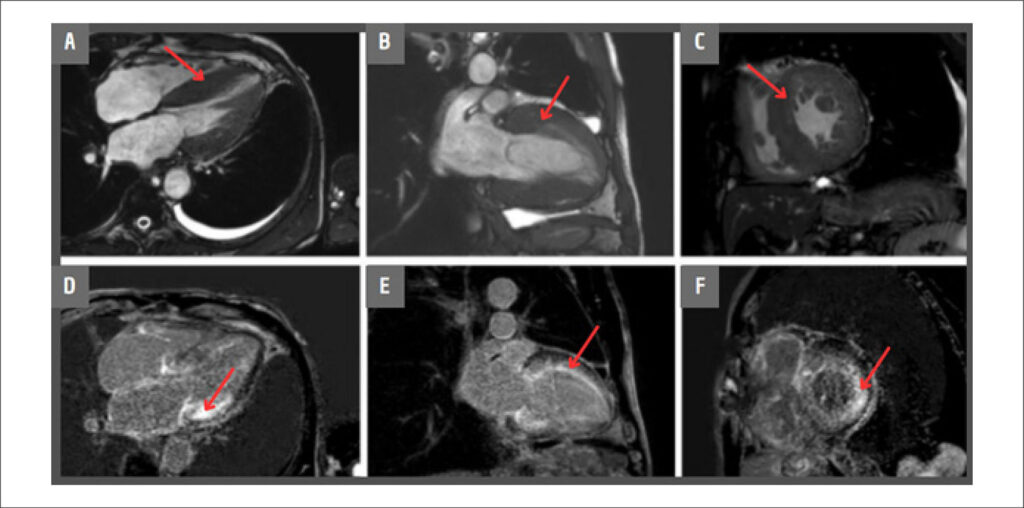

Cardiac Amyloidosis is a restrictive cardiomyopathy caused by the accumulation of amyloid protein in the heart. The advances in non-invasive diagnosis have been increasing its identification among patients with Heart Failure (HF), being previously considered to be a rare condition. Currently, it represents around 13% of the cases of Heart Failure with preserved Ejection Fraction (HFpEF). We report the case of a 72-year-old male patient who presented to the clinic reporting dyspnea and fatigue in low-effort activities. Laboratory exams were conducted, revealing increased cardiac markers, along with evidence of ventricular hypertrophy in electrocardiographic analysis. Cardiac imaging, serum free light chain (AL) assay, and endomyocardial biopsy indicated the diagnosis of AL amyloidosis. A three-dimensional model was constructed using magnetic resonance imaging (MRI) data. This model is intended to increase the awareness around amyloidosis as a possible differential diagnosis of HF, while also promoting patients’ and families’ education, demonstrating the typical structural abnormalities of the disease.